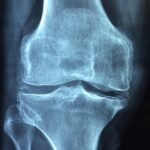

Zu viel Harnsäure kann zu Gicht führen

Ist der Harnsäurewert im Blut dauerhaft erhöht, kann dies zu einem Gichtanfall führen. Er ist ein Zeichen dafür, dass sich Harnsäurekristalle im Gelenk angesammelt und zu einer schmerzhaften Entzündung geführt haben. Bei den Gelenken sind meistens Füße oder Hände betroffen. Die Harnsäurekristalle lösen dort eine Entzündung aus, wodurch die Gelenke anschwellen, warm werden und schmerzen. Die Entzündung klingt in der Regel innerhalb von ein bis zwei Wochen ab. 2,3,17

Ein hoher Harnsäurespiegel führt jedoch nicht zwangsläufig zur Gicht, sondern erhöht lediglich das Risiko. Dies mag daran liegen, dass andere Faktoren hinzukommen müssen. So wurde festgestellt, dass sich die Harnsäurekristalle vor allem dann in den Gelenken bilden, wenn sie zu wenig Gelenkflüssigkeit haben. Auch der pH-Wert der Gelenkflüssigkeit und die Temperatur des Gelenks spielen eine Rolle. Die Menge der Gelenkflüssigkeit hängt übrigens mit der täglichen Flüssigkeitszufuhr zusammen. Auf diese Weise können sich Harnsäurekristalle auch in den Nieren ablagern (Uratnephropathie). Gemäß IQWiG bestehen 5 bis 10% der Nierensteine aus Harnsäure.3,8,18–21

Für die langfristige Gesundheit stellen erhöhte Harnsäurewerte durchaus eine Gefahr dar. Immerhin können Gichtanfälle zu einer chronischen Gicht führen, wodurch die Gelenke geschädigt und in der Folge die Muskeln geschwächt und die Beweglichkeit eingeschränkt werden.

Liegen Schmerzen und Schwellungen in den Gelenken vor, die ein bis zwei Wochen anhalten, sollte nach Abklingen der Beschwerden beim Hausarzt der Harnsäurewert mittels Blutanalyse untersucht werden. Misst man den Harnsäurespiegel während eines akuten Anfalls, kann es sein, dass der Wert im Blut normal ist. Für die sichere Diagnosestellung muss das Gelenk punktiert werden, um die Harnsäurekristalle im Gelenk nachweisen zu können. In vielen Fällen begnügt man sich jedoch auch damit, anhand des erhöhten Harnsäurespiegels und des Beschwerdebildes die Diagnose zu stellen.2,3